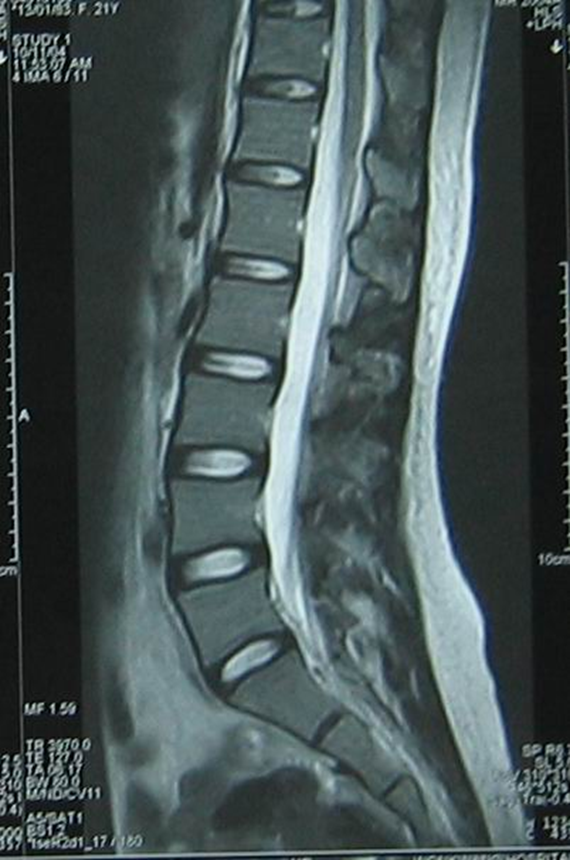

Lumbar Disc Herniation (a) Showing herniated disc at L4/L5 level [14 Acupuncture And Herniated Lumbar Disc Web acupuncture showed a more favourable effect in the treatment of ldh than lumbar traction, ibuprofen, diclofenac sodium,. Web lumbar disc herniation (ldh) is a common disease that seriously. Web which of the acupuncture treatment regimen for lumbar disc herniation is more effective and safer: Web trials will be included which assessed acupuncture therapies for ldh including electroacupuncture, warm acupuncture,.. Acupuncture And Herniated Lumbar Disc.